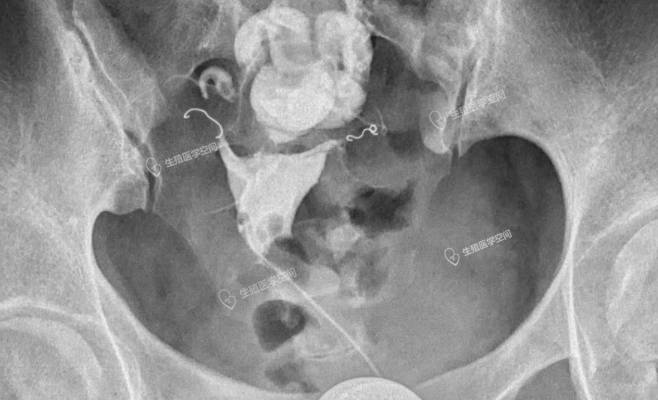

一、评估一下输卵管的粘膜功能是否正常,如果伞部和壶腹部粘膜功能大致正常(图1),就做输卵管积水伞端造口术。如果输卵管粘膜少或无,导致输卵管生殖功能丧失(图2),就直接做试管婴儿。

所谓的致密栓塞,就是栓塞多个弹簧圈。在栓塞手术的当时如果多个弹簧圈并联栓塞在一起,使输卵管管腔明显扩张,有可能超过肌肉的扩张限度,肌肉再也回缩不回来了,就不能封闭输卵管管腔,达不到栓塞的目的。就向橡皮筋拉的太长,失去弹性,再也没有收缩能力了,只能扔掉。即使输卵管管腔的扩张没有超过肌肉的扩张限度,术后每个弹簧圈都是各自回缩,就会出现弹簧圈移位或弹簧圈之间形成间隙不能封闭输卵管管腔(图4,图5和图6)。如果多个弹簧圈栓塞串联在一起,比邻的弹簧圈互为支架,支撑起输卵管管腔使管腔持续扩张,弹簧圈不仅容易移动,而且两端也不易回缩封闭管腔,输卵管管腔封闭的也不严实(图4,图5和图6)。而且弹簧圈移动输卵管管腔的纤维组织不容易增生。因此致密栓塞不仅是多花钱多受罪,而且还没有栓塞一个合适的弹簧圈栓塞的严实。

这两例都是所谓的致密栓塞,手术的医生自己也不自信,栓塞后手术结束前也不敢做一个造影看看效果。图4手术费花了1万9千多,右侧输卵管前几个弹簧圈掉进了宽大的积水管腔,没用一点栓塞作用。左侧输卵管栓塞是串联加并联。图5手术费是2万4千多,双侧输卵管栓塞的前几个弹簧圈都掉进了远段宽大的积水管腔,没用一点栓塞作用,起作用的就是最后一个弹簧圈。